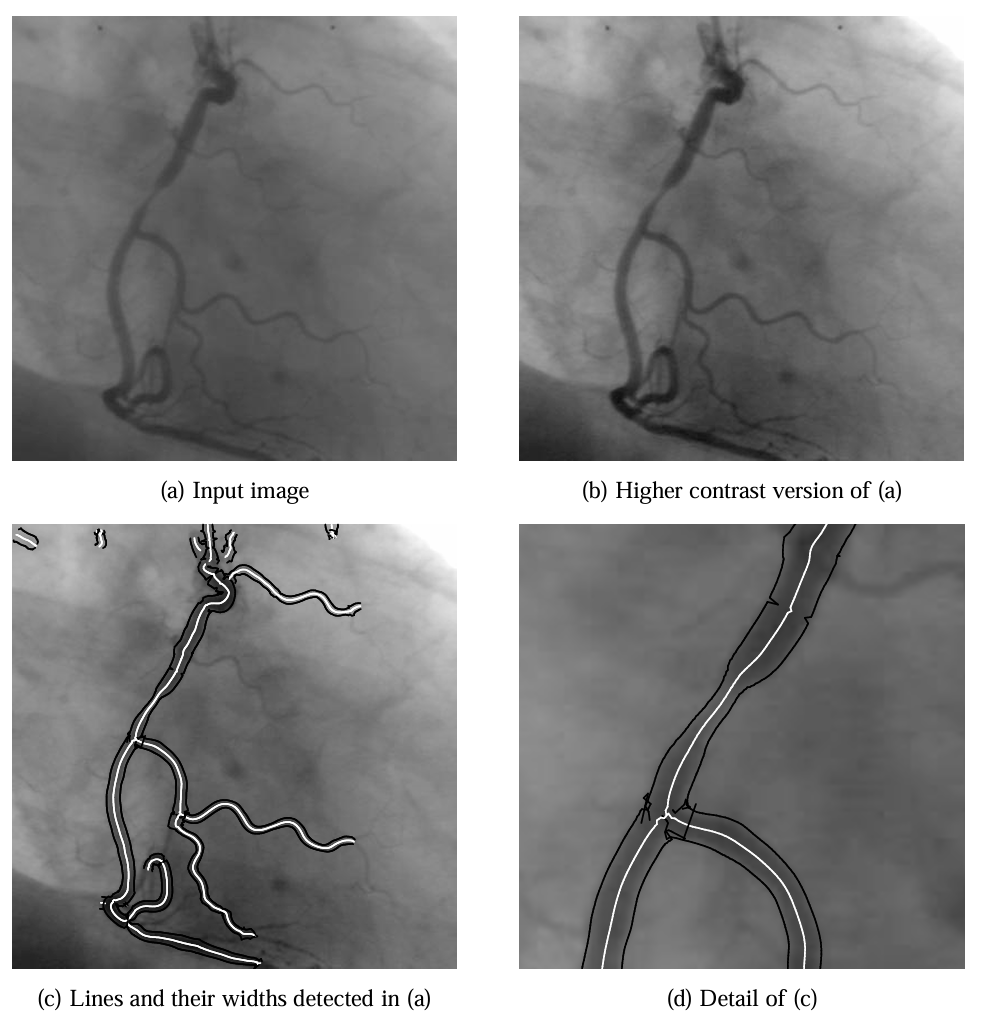

医学成像示例中,图 19(b) 的 MR 图像线条提取结果显示,颅骨和其他特征的位置与宽度精度较高,而未消除偏差的图 19(d) 在脑回区域因线条非对称性导致位置偏差。冠状动脉血管造影图 20 中,算法成功描绘血管狭窄区域,显示出在低对比度医学图像中的有效性。

图 20:在冠状动脉血管造影图 (a) 中检测到的线条。由于图像对比度低,从 (a) 提取的结果 (c) 叠加在对比度更好的图像 (b) 上。(d) 为 (c) 的三倍放大细节